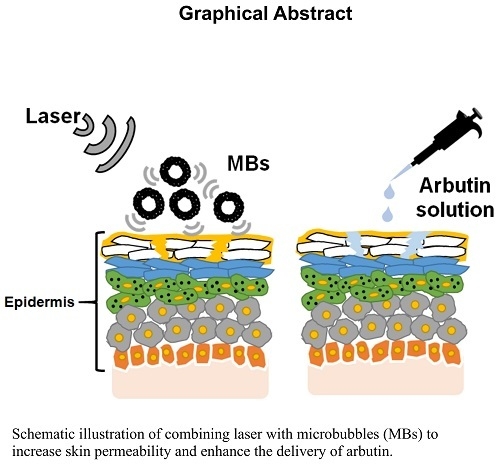

Combining Microbubble Contrast Agent with Pulsed-Laser Irradiation for Transdermal Drug Delivery

Abstract

:1. Introduction

5. Conclusions